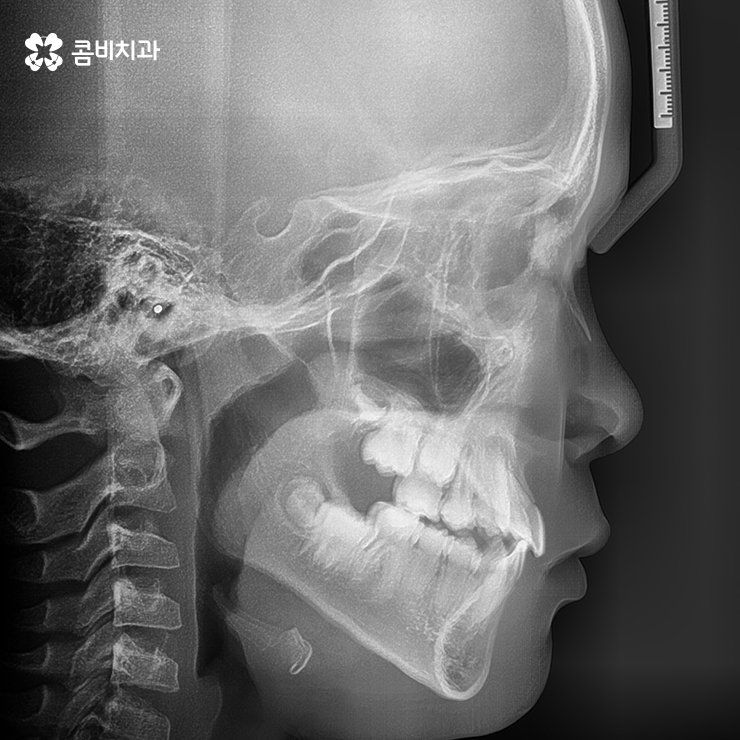

구강검진을 통해서 이러한 골격 부조화를 조기에 발견하여

치료를 시작할 경우 아래턱은 성장을 억제시키고

위턱은 성장을 유도하는 TTBA라고 하는 성장기 교정 장치를

활용하여 주걱턱의 교정이 비수술적인 방법으로 가능합니다.

만약 이러한 반대교합이 있는 상태로 성인이 되어 성장이 멈춘다면

흔히 양악 수술이라 불리는 수술을 치아교정과 병행해야 할 수 있기

때문에 성장기치아교정이 가능한 시기를 잘 활용하는 것이 좋습니다.